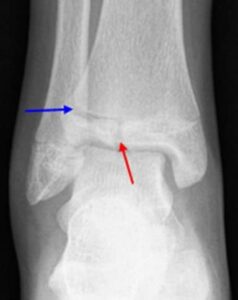

In children and adolescents, ankle fractures typically affect the tibia or fibula, often involving the growth plates—specialized areas of cartilage near the ends of long bones. Growth plates play a critical role in bone development, gradually hardening into solid bone as the child matures. However, because these growth plates are the last parts of the bones to solidify, they are particularly prone to injury and fractures. As adolescents approach the end of their growth phase, growth plates begin to close and harden, making them susceptible to transitional fractures during this maturing stage. Two common types of transitional ankle fractures are triplane fractures and Tillaux fractures, which require specific treatment approaches depending on their severity and location (refer to the Treatment section for more details)